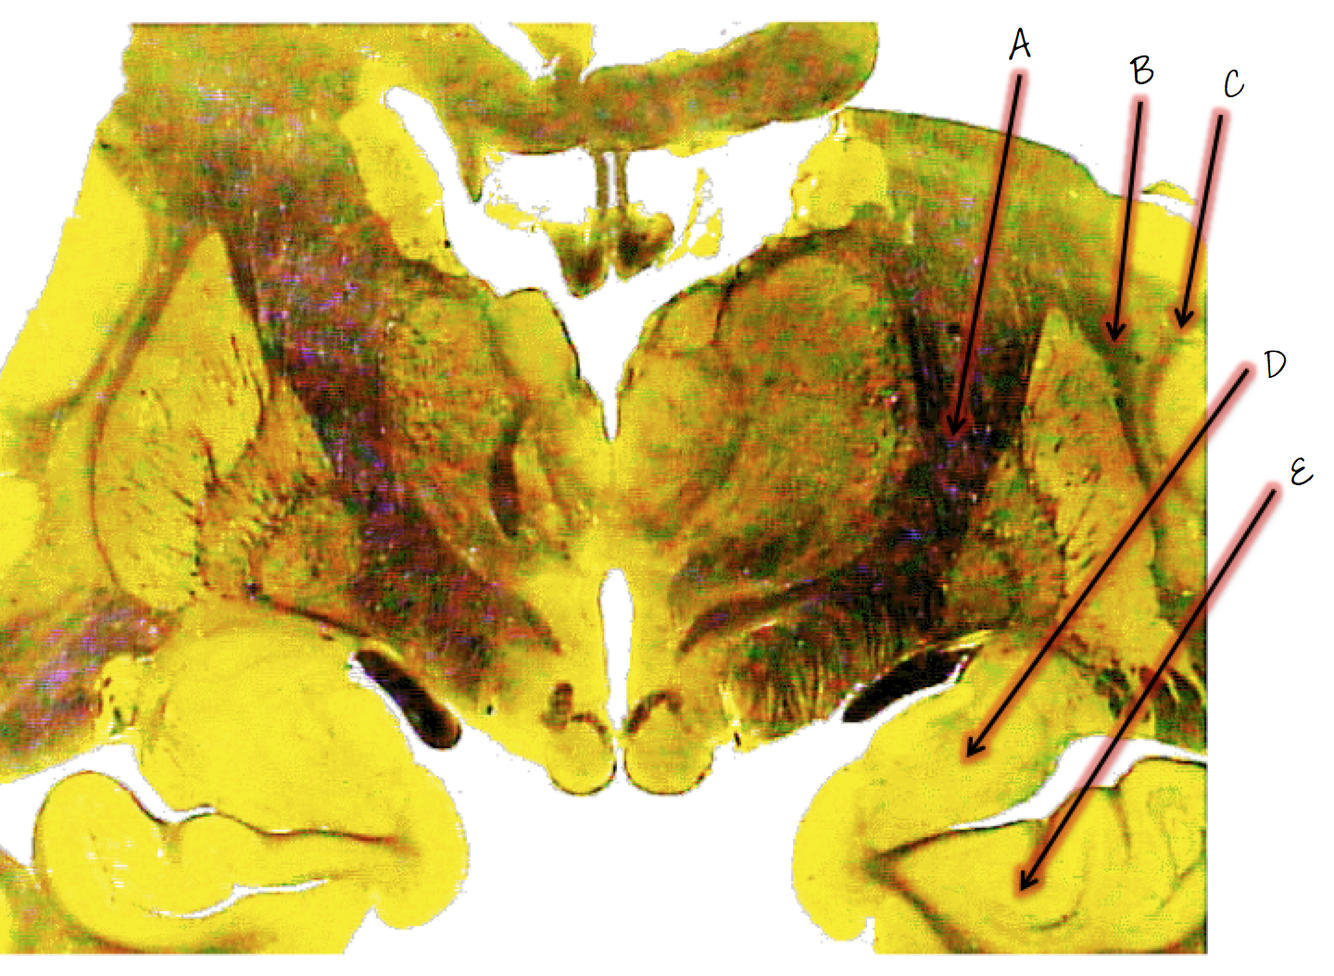

A; pulvinar

B; medial geniculate body

C; lateral geniculate body